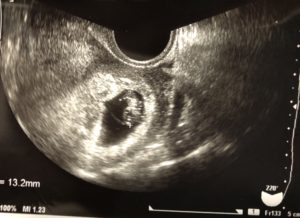

そしてエコーへ。

今回はそれ程時間がかからずにカーテンが開きました。

もしかして…⁉︎

「正常だね。もう心拍も見えるよ」

胎芽だけでなく、心拍も確認出来て少し涙ぐみました。